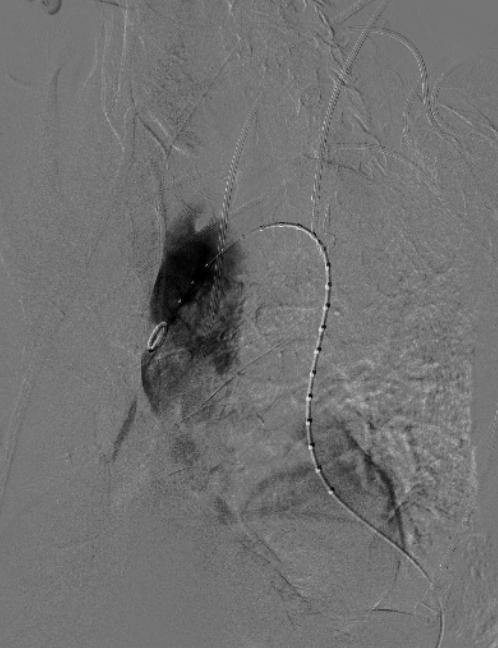

术后造影

术后造影显示,主动脉夹层第一破口被有效隔绝,迷走左椎动脉与LSA血流通畅,胸降主段真腔得到重塑,支架无移位或内漏现象发生,手术圆满成功。

治疗车怎么推「弓部重建直通车」鄂尔多斯市中心医院康巴什部介入科运用Castor®分支型支架联合预开窗技术治疗Stanford B型胸主动夹层_https://www.jmylbn.com_新闻资讯_第11张